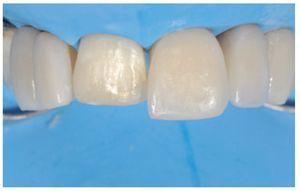

Una vez acabada la preparación cavitaria, la matriz de silicona permitió visualizar la forma, el grosor, las futuras dimensiones y las correctas relaciones interproximales.

Esto es una ayuda importante, ya que consigue que el trabajo sea predecible, permite gestionar bien el tiempo y limita el tiempo de trabajo en el sillón. Asimismo, las matrices transparentes seccionales con múltiples convexidades (KerrHawe, Bioggio, Suiza) también son una ayuda útil en el manejo del tiempo, ya que permiten al clínico crear de forma sencilla e intuitiva unos perfiles de emergencia correctos. Éstas son las herramientas para gestionar de forma correcta la configuración de las restauraciones, eliminando cualquier exceso de material que conllevaría intervenciones de remodelado laboriosas y difíciles, con el riesgo añadido de dañar los dientes adyacentes y perder los puntos de contacto. Una matriz seccional es un medio útil para restaurar la anatomía interproximal gracias a su elasticidad intrínseca, que hace que sea altamente adaptable a un gran número de morfologías dentales (figuras 38 y 39). Asimismo, ayuda a evitar la contaminación accidental de los dientes adyacentes durante las fases de grabado y adhesión (figura 40). La aplicación combinada de una llave estable y matrices seccionales permite al clínico manejar de forma sencilla e intuitiva incluso las formas dentales más complejas en un único paso, optimizando así tanto el tiempo de trabajo como el resultado final (figuras 41-44).

Figura 38 Uso de una matriz seccional transparente para restaurar los perfiles de emergencia y puntos de contacto correctos.

Figura 39 Paso de estratificación, cavidad de clase III en diente número 22.